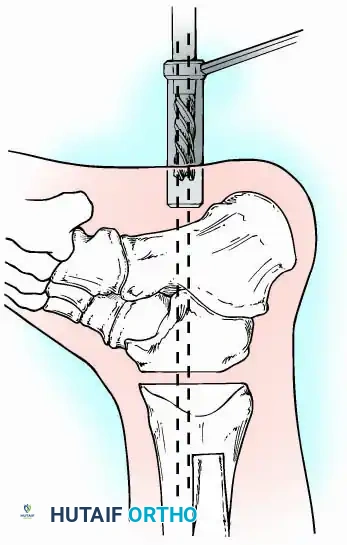

Internal fixation is currently the preferred method for uncomplicated ankle arthrodesis due to higher union rates, superior patient comfort, and the elimination of pin-tract infections. Biomechanical studies demonstrate that crossed, large-diameter (6.5 mm or 7.3 mm) cannulated cancellous screws provide exceptional resistance to shear and torsional forces.

A standard construct involves two or three screws:

1. A "home run" screw directed from the posterior malleolus into the anterior neck of the talus.

2. A screw from the medial malleolus into the lateral body of the talus.

3. A screw from the anterolateral tibia into the medial talar body.